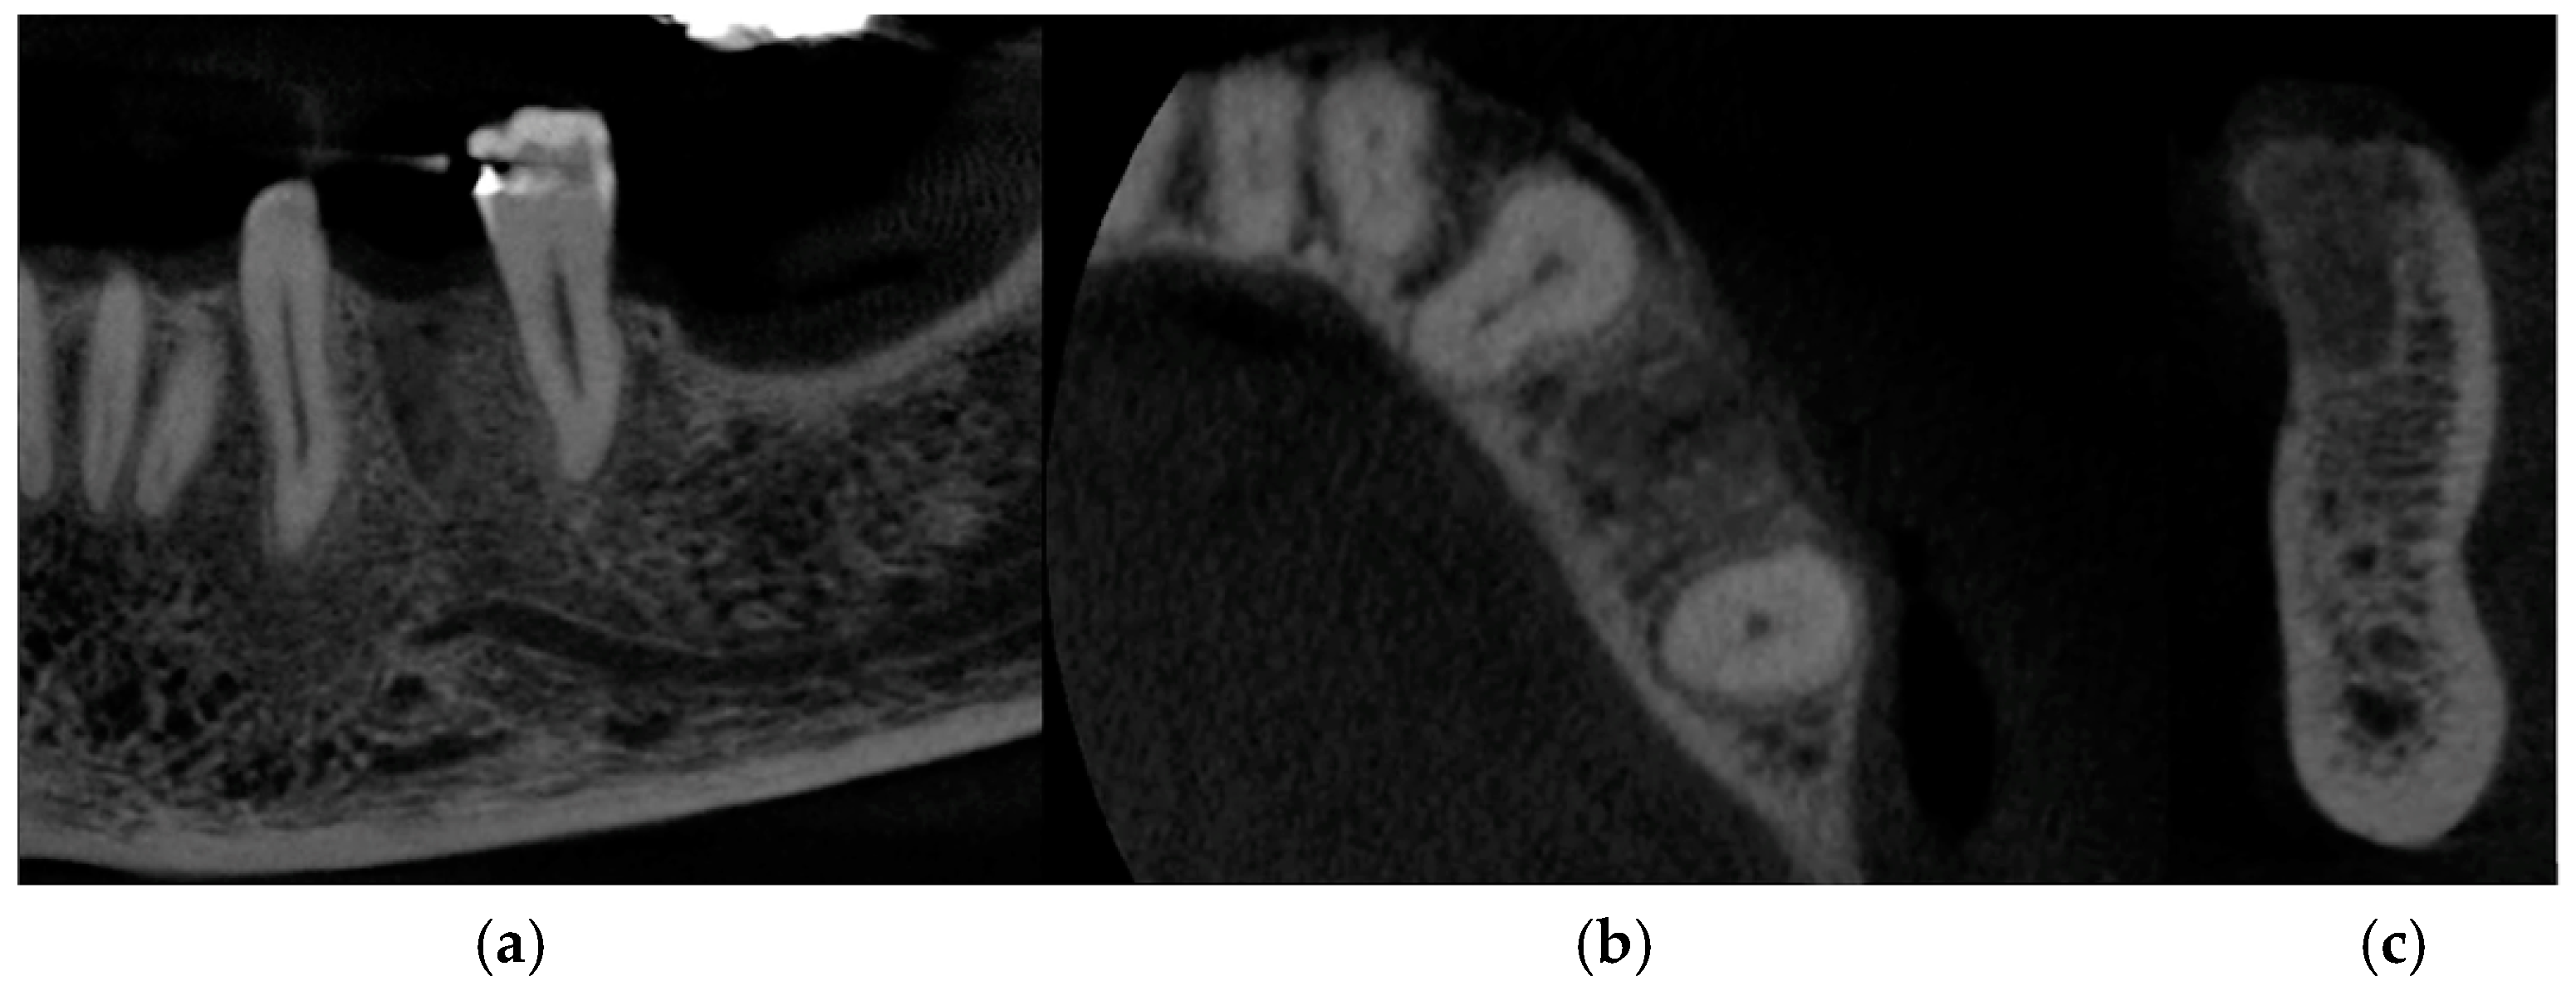

At 4 months, CBCT was performed to check the hard tissues, which confirmed a correct healing pathway with maintenance of the initial dimensions (Figure 4a–c).

Figure 4. CBCT images at 4 months after the surgery: (a) frontal section, (b) transversal section, and (c) sagittal section.